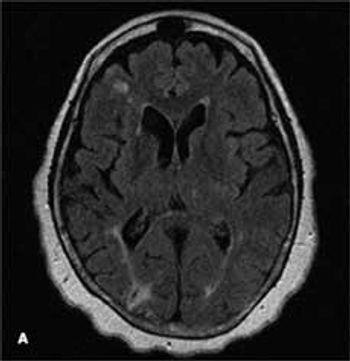

A 68-year-old woman with a history of hypertension, hyperlipidemia, and tobacco use presented with her third stroke in the past 7 years. Neurological deficits included dysarthria and left-sided motor and sensory loss. A previous transthoracic echocardiogram with a bubble study did not reveal any cardiac source of embolism. Axial MRI of the brain on admission showed an abnormal signal in the bilateral hemispheres representative of multiple subacute infarcts